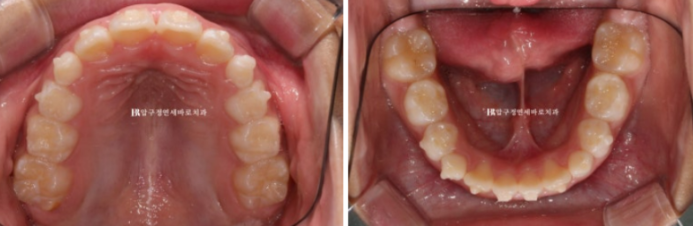

23.09

좁았던 입천장 악궁이 넓어졌고 앞니 배열이 가지런해졌습니다.

클린체크 치료계획상 25단계 장치에서 기대되는 치열이고 치료경과가 좋아서 실제 입안 상태도 비슷합니다.

이제 본격적으로 무턱에 대한 성장교정을 시작할 단계입니다.